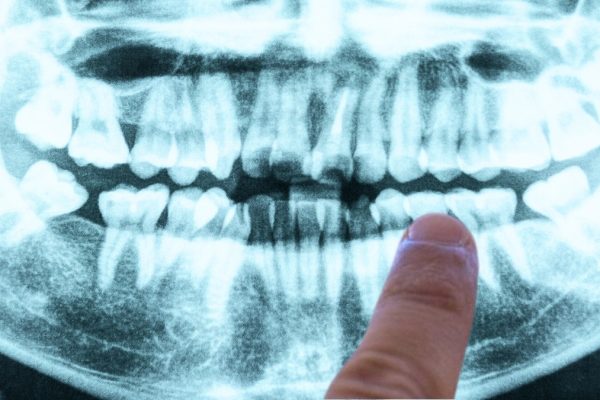

Cum Problema Alzheimerului Ar Putea Avea Radăcini în Propria Ta Gură

Deși mecanismele exacte ale acestei infecții sunt încă în curs de isolare de către cercetători, numeroase studii sugerează că apariția letală a bolii Alzheimer depășește cu mult ceea ce credeam anterior. Un studiu din 2019 a sugerat ceea ce ar putea fi una dintre cele mai definitive dovezi până acum pentru a identifica o bacterie…